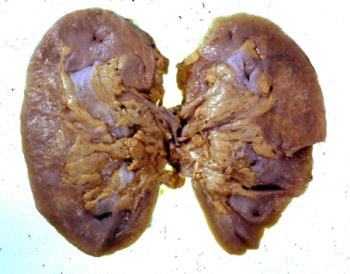

- Renal failure following uraemic ulceration of colon Clinical history: From a male aged 54 years. Admitted to hospital for investigation of headaches, with tiredness and lassitude. The patient was a known case of prostatic carcinoma, he was treated with oestrogens. Shortly after admission complained of lower abdominal pain of colicky character and began to pass diarrhoea with fresh blood. Was examined by sigmoidoscope, then a laparotomy was carried out, and the diagnosis of procto-colitis made. Following operation he never show improvement. he was known to be hypertensive, and retinae bore this out; renal function tests indicated very considerable impairment, and soon renal output shrank to nil, B.U.N. rose, and despite electrolyte imbalance being fairly adequately maintained he died. Post mortem findings: Genito-urinary system Both kidneys were reduced to less than half their normal bulk and each weighed 60 gms. Their capsules stripped readily to reveal a granular surface. On sectioning they showed marked reduction in cortical bulk and marked yellow pigmentation of tubules, presumably due to lipoid accumulation. The cortex was otherwise paler than normal and the appearances suggested an advanced degree of chronic nephritis. The calyces, pelvis, ureters were normal, the bladder was hypertrophied but was not inflamed and the prostate, which remained showed no macroscopic evidence of tumour. Alimentary system Tongue, pharynx: n.a.d. The oesophagus showed a mild degree of oesophagitis. The stomach and duodenum showed no change of note. The uppermost part the jejunum was rather congested and in many places in jejunum there were small, submucosal haemorrhages. In the mid portion of the jejunum several shallow. uraemic ulcers were present in the gut. Some portions of the ileal mucosa were congested but no ulcers were present in the ileum and in general the ileum looked much healthier than the jejunum. There was an abrupt change at the ileo-caecal valve however and the caecum showed very marked uraemic ulceration, which involved approximately 2/3 of the mucosa of the caecum. The ulcers were shallow and, were covered by a yellow-grey exudate. The mucosa of the appendix appeared normal. The gross uraemic ulceration continued for some distance into the ascending colon and from that point onwards to just passed the splenic flexure the mucosa was generally congested and there was a line of uraemic ulceration similar to that in the caecum along each taenia coli. No ulceration was detected in the pelvic colon or rectum and the mucosa appeared relatively healthy. The peritoneal cavity was normal. The liver weighed 1500g., was of normal shape, but on sectioning showed marked pallor due to anaemia and possibly also due to fatty change. Cardiovascular system: The pericardial sac was normal. The heart weighed 420 gms. and showed a moderate degree of left ventricular hypertrophy. The coronary arteries were rather atheromatous and one small focus about cm. diameter of fibrosis was detected in the left ventricular myocardium on the lateral walls The cardiac valves showed no significant abnormalities the other chambers were dilated There was a valvular patency of the foramen ovale and the upper portion of the septum secundum was fenestrated. Neither of these were likely to have caused any functional improvement during life. The aorta showed a relatively mild degree of atheroma, the pulmonary artery contained no thrombi.

Weight: Kidney (each) 60 g